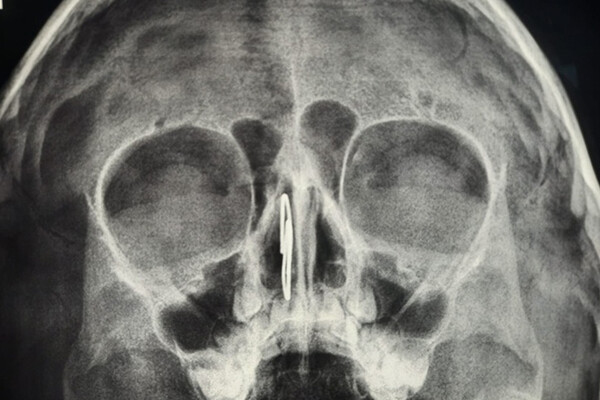

Во Владимире врачи достали из носа дошкольника скрепку

Врачи Областной детской клинической больницы во Владимире помогли четырехлетнему мальчику, который заигрался и засунул себе в нос скрепку. Об этом сообщили в пресс-службе медицинского учреждения.